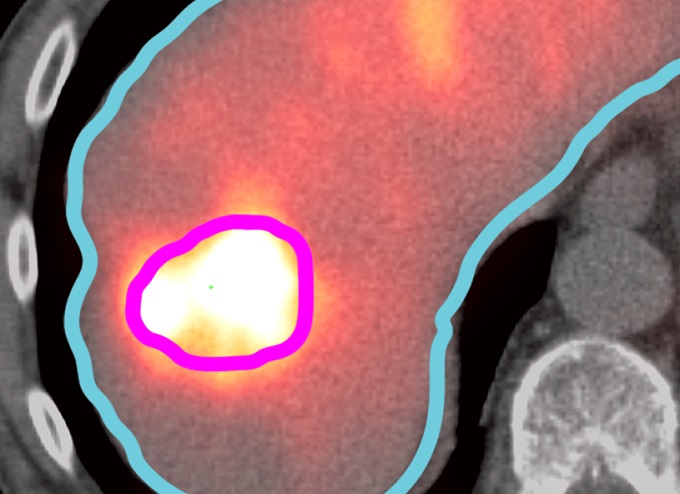

INSYTE with SurePlan LiverY90

Our collaboration with MIM Software Inc. means we are able to provide you with SurePlan LiverY90.  This software provides timesaving tools and post-treatment dosimetry for interventional radiologists and nuclear medicine physicians treating hepatic tumors with SIR-Spheres.